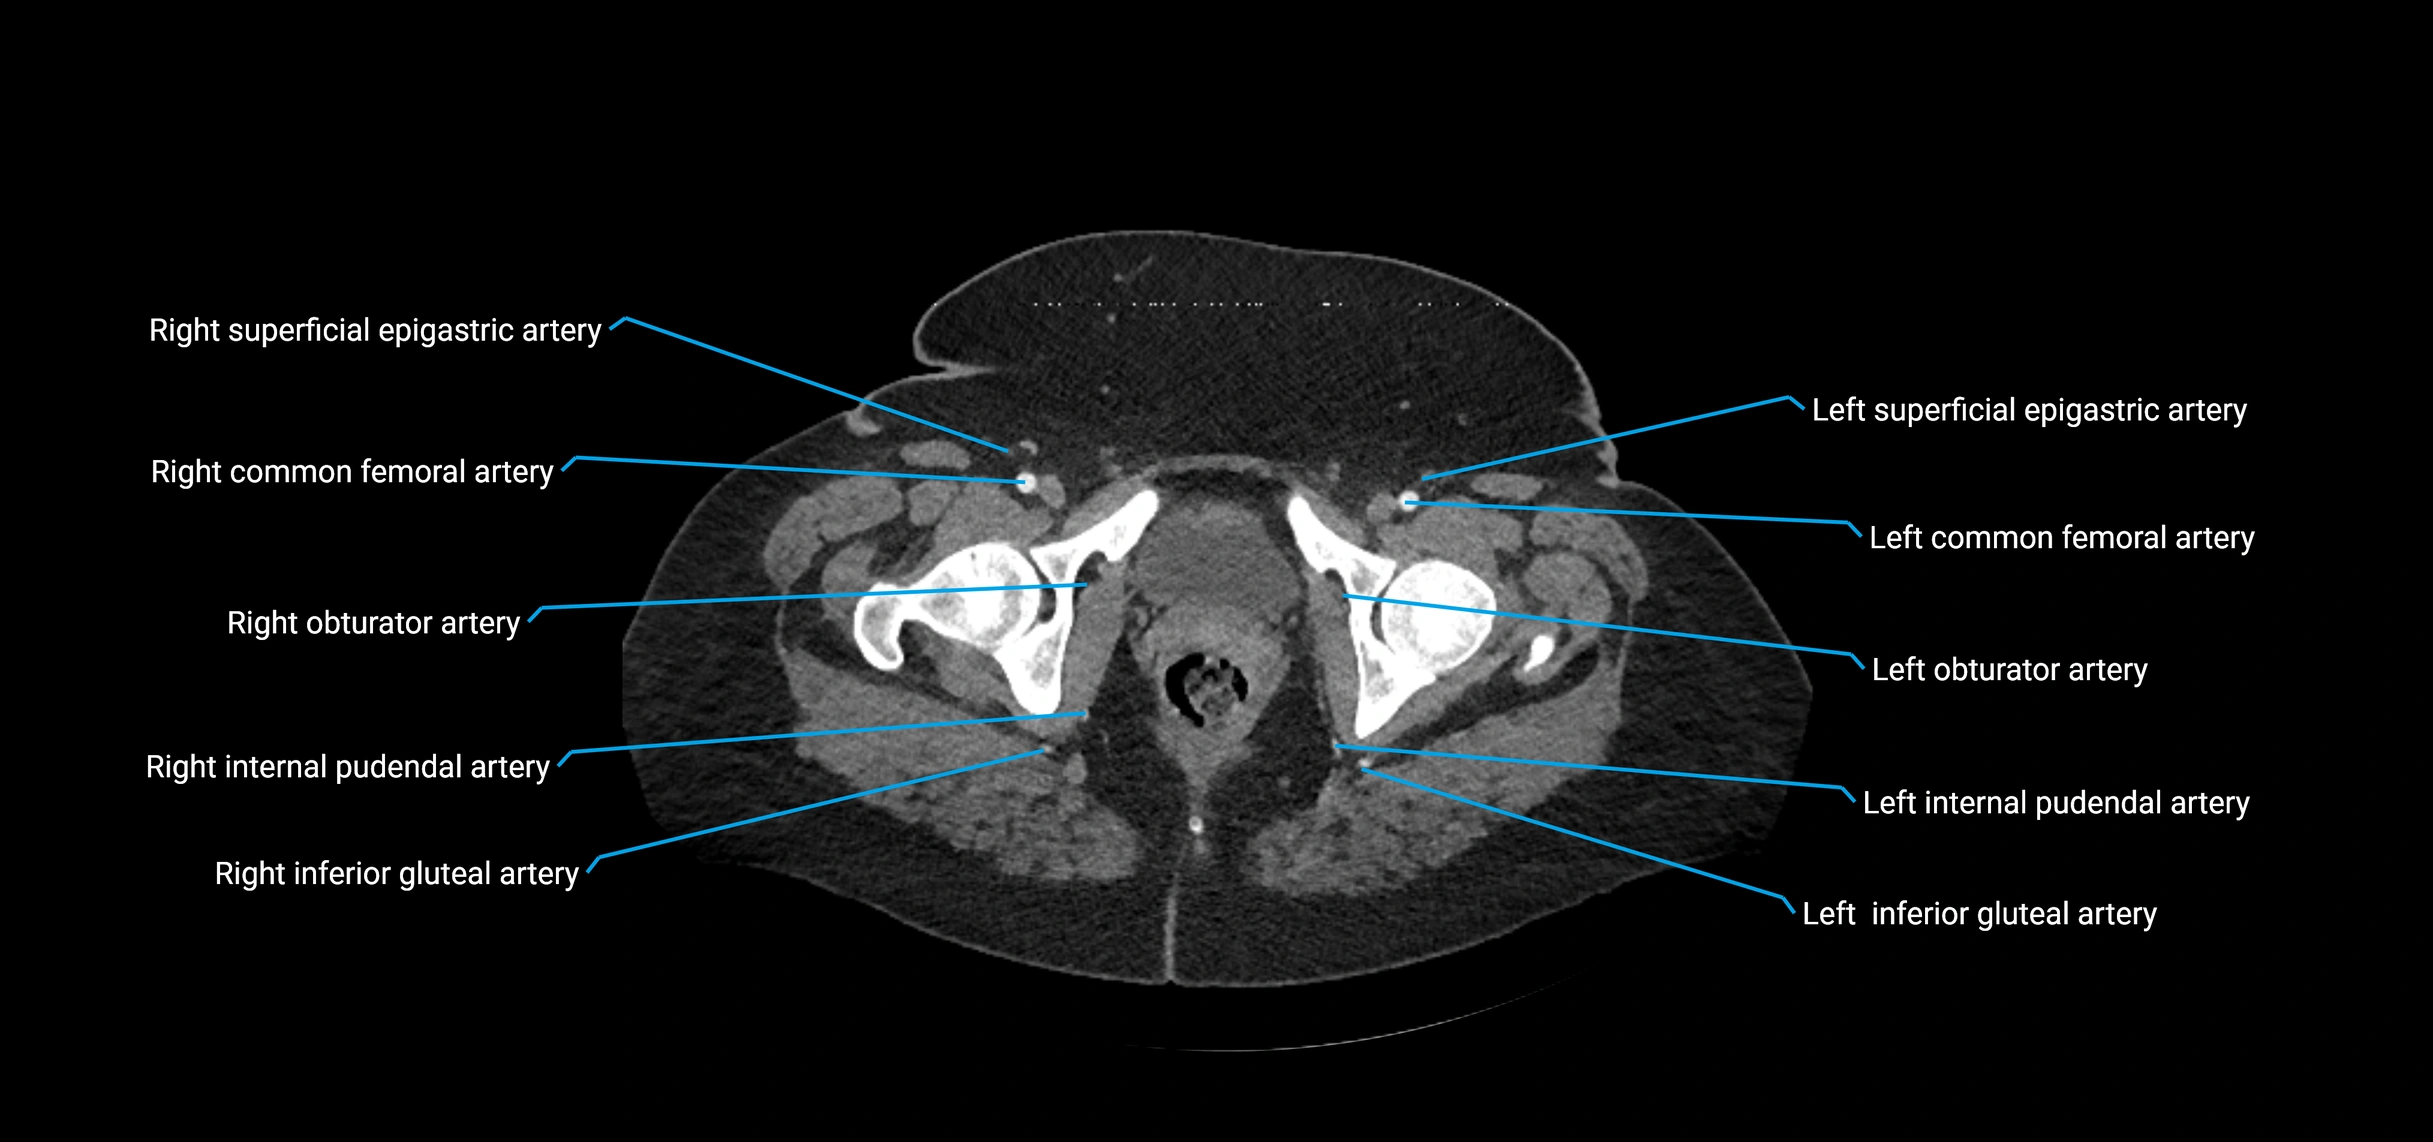

Contrast-enhanced CT (CTA):

• Gold standard for abdominal aortic imaging

• Provides excellent detail of lumen, wall, aneurysm, thrombus, and branch vessels

• Multiplanar and 3D reconstructions help in aneurysm measurement, stent graft planning, and dissection evaluation

• Detects acute rupture, traumatic injury, or occlusion with high sensitivity